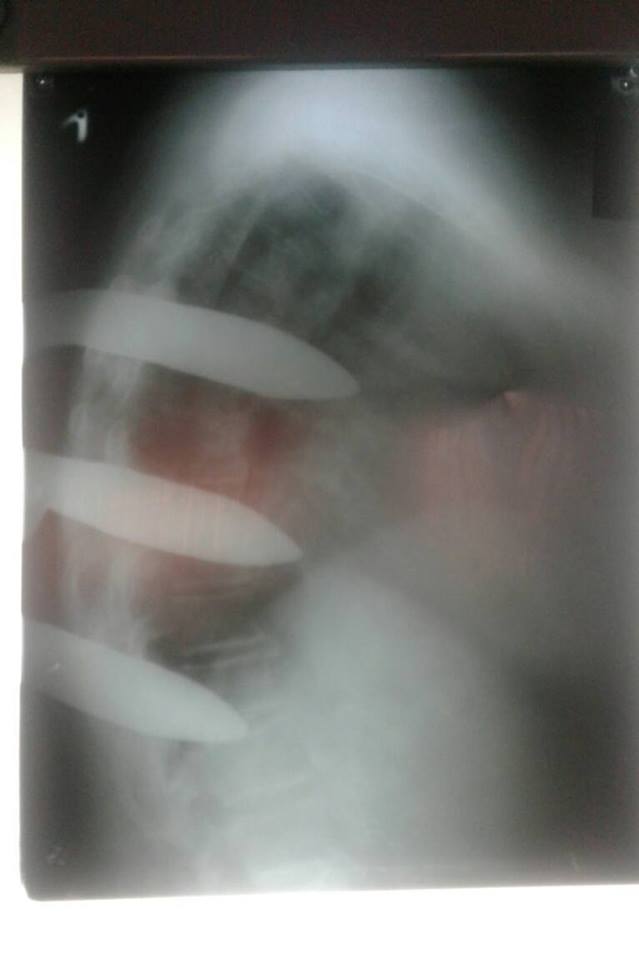

У Ковелі до лікарні потрапила жінка, у спині якої був металевий інструмент.

«Вкотре нашим лікарям довелося зіткнутися з неординарним випадком – стороннє тіло м'яких тканин задньої поверхні тулуба. Травма побутова, з необережності», - пишуть медики.

Також зазначають, що наразі стан пацієнтки стабільний.